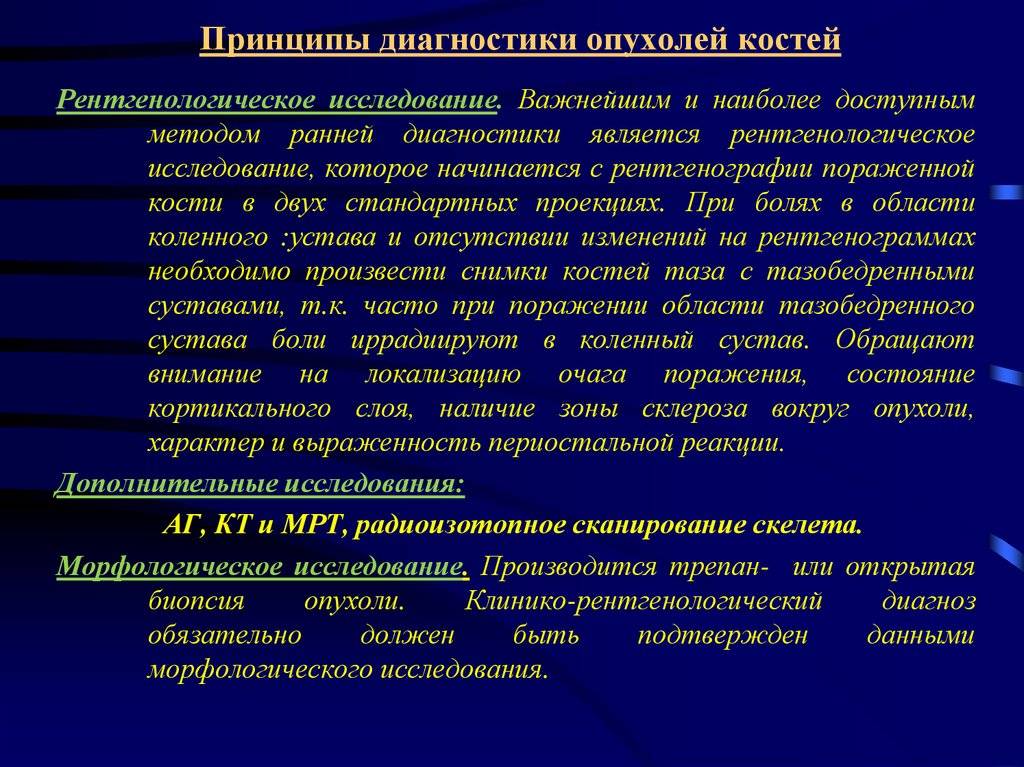

Понятие онкологической настороженности. Онкологическая настороженность в стоматологии презентация. 7 «Сигналов» злокачественной опухоли. Настороженность по онкологии. Алгоритм диагностики опухолей. Методы диагностики опухолей костей. Методы выявления опухоли. Методы диагностики злокачественных опухолей.

Алгоритм диагностики опухолей. Методы диагностики опухолей костей. Методы выявления опухоли. Методы диагностики злокачественных опухолей. Методы диагностики опухолей. Метод диагностики опухолей. Методы выявления опухоли. Методы диагностики злокачественных опухолей.

Методы диагностики опухолей. Метод диагностики опухолей. Методы выявления опухоли. Методы диагностики злокачественных опухолей.